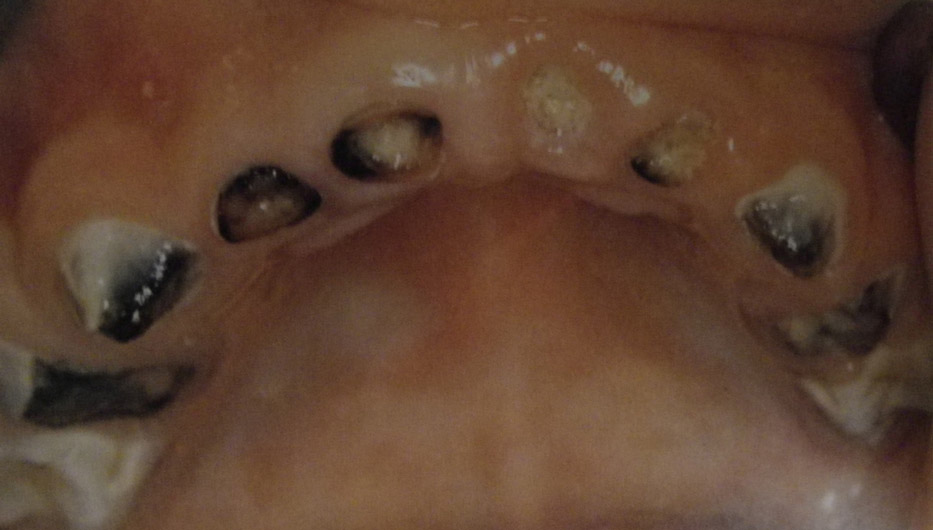

Τερηδόνα βρεφικής και νηπιακής ηλικίας ή τερηδόνα θηλασμού

Η τερηδόνα βρεφικής και νηπιακής ηλικίας εμφανίζεται σε μικρά παιδιά ηλικίας 2 έως 5 ετών, τα οποία έχουν τερηδονισμένα ένα ή και περισσότερα νεογιλά δόντια. Η τερηδόνα αυτής της μορφής οφείλεται σε λάθος τρόπο διατροφής του παιδιού και μπορεί να εξελιχθεί γρήγορα και σε μεγάλη έκταση επηρεάζοντας το σύνολο το δοντιών που βρίσκονται στο στόμα.

Η κυριότερη αιτία εμφάνισης της τερηδόνας αυτής της μορφής είναι το τάισμα με το μπιμπερό ενώ το παιδί κοιμάται. Κατά τη διάρκεια του ύπνου η ποσότητα του σάλιου μειώνεται και το γάλα, ανεξάρτητα αν περιέχει ή όχι ζάχαρη, παραμένει πάνω στα δόντια και προκαλεί τερηδόνα. Ακόμη και το μητρικό γάλα μπορεί να έχει τις ίδιες συνέπειες, εφόσον το παιδί θηλάζει κατά βούληση κατά τη διάρκεια της νύχτας.